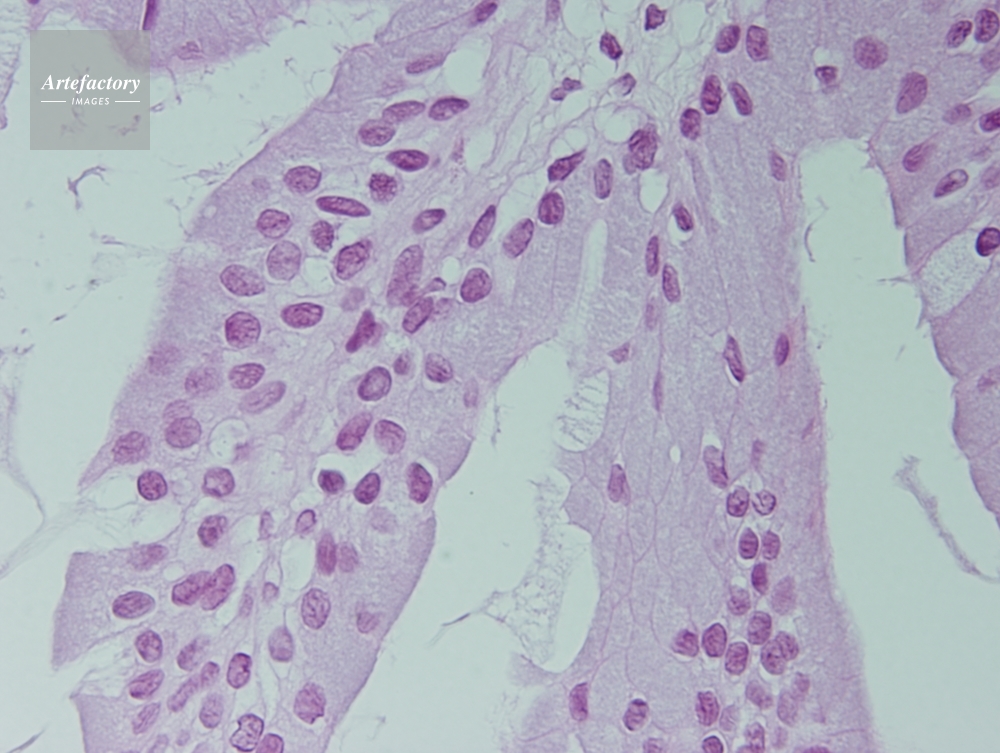

| 作品タイトル | カエル,舌 | モデルリリース | なし | |

| 作家 | OLYMPUS CORPORATION Technolab | プロパティリリース | なし | |